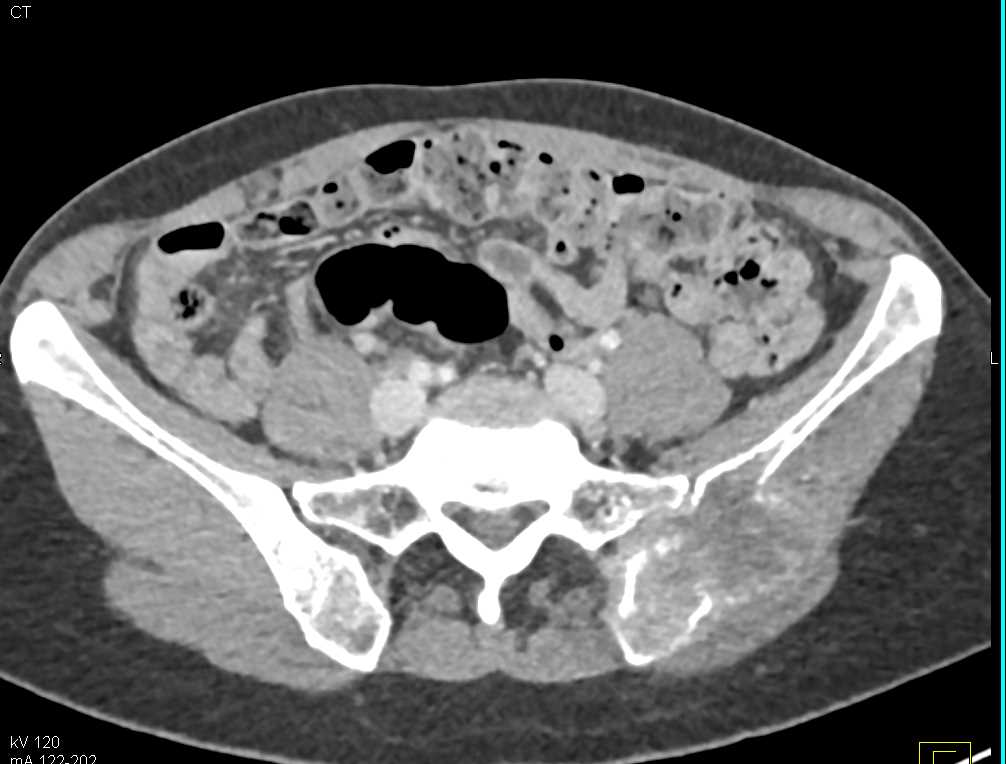

Papillary Renal Cell Carcinoma Right Kidney